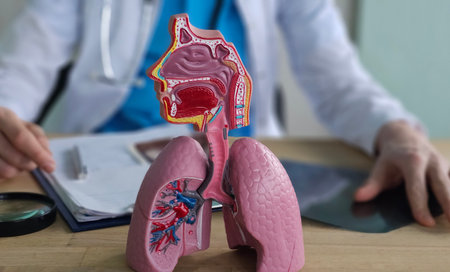

Medical model of human respiratory system displayed during consultation with doctor in clinic

Human respiratory system showing lungs and trachea placed on a desk near educational materials